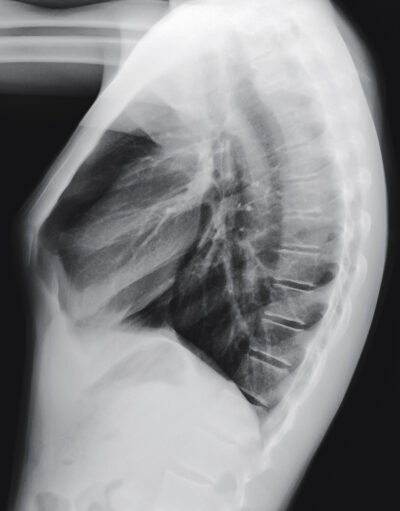

Pectus Carinatum

Pectus carinatum is a deformity of the chest in which the breastbone protrudes outwards. The bulging gives the chest a birdlike appearance which is why the condition is sometimes referred to as pigeon chest. It occurs when the cartilage that holds the ribs to the breastbone has a defect, and the cartilage pushes the breastbone and ribs outwards causing the chest to jut outwards. It is unknown what causes this chest deformity, but is believed to be genetic in nature.

While the condition is categorised by the protrusion of the breastbone forwards, pectus carinatum is often only developed during early adolescence when the growth spurt hits. It is then that the symptoms worsen and the physical deformity begins to show.

The symptoms should begin to show in the early teen years, only getting worse and worse as the child grows. Since these symptoms are caused by the protrusion of the breast bone, it may require surgery to treat. Treatment of pectus carinatum is possible at a very early age with an external brace. If surgery is required, the best time would be at the time of the adolescent growth spurt.